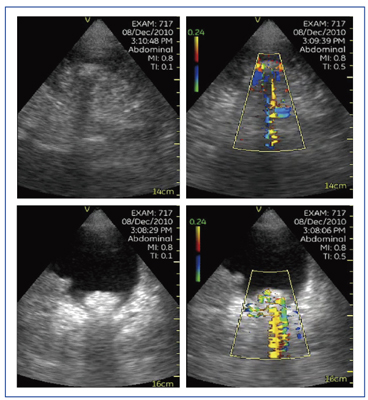

図6は,肝硬変で門脈に血栓があり,門脈内に血流がないことが認められた症例である。Vscanのモニタは小さいが高画質であり,医師自身の観察力を高めることで,より多くの情報を得ることが可能となる。

図6 症例1:肝硬変+門脈血栓